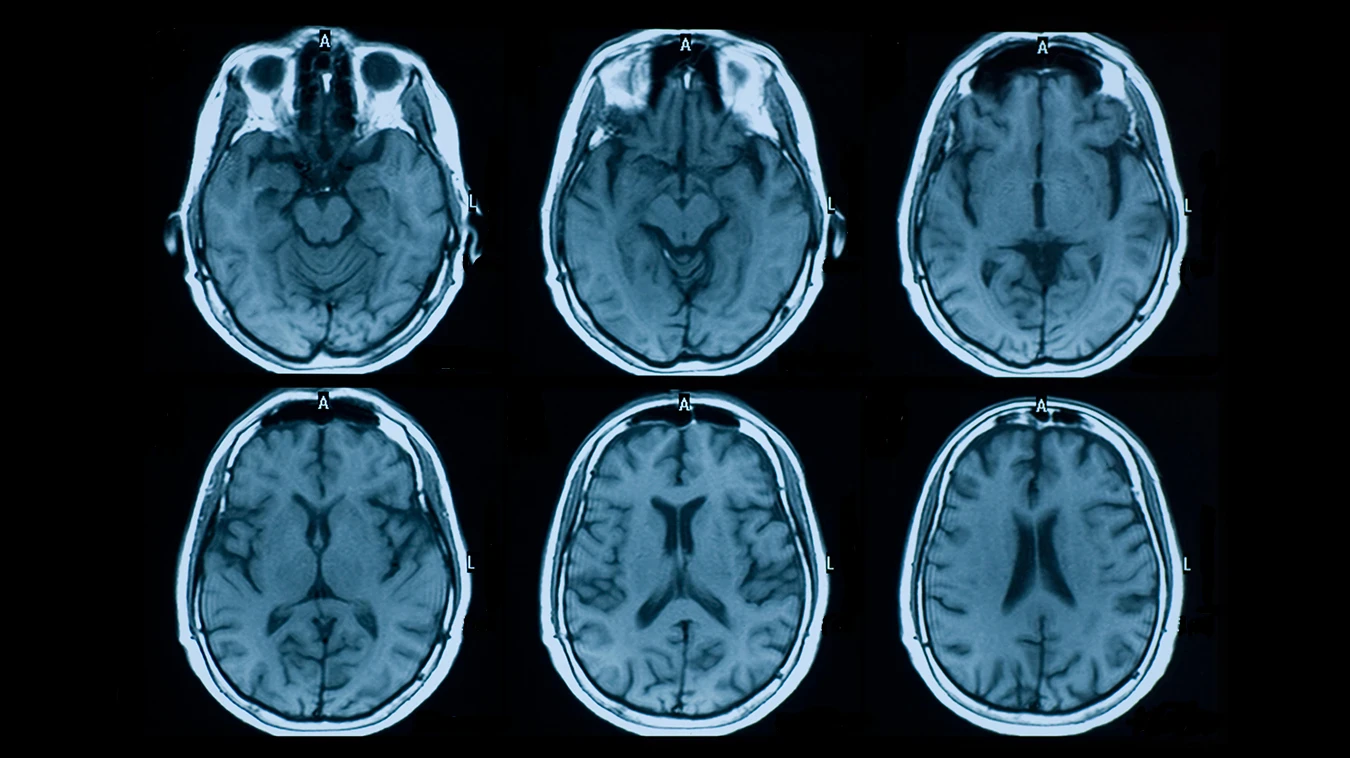

يعتبر التصلب المتعدد (Multiple Sclerosis) من أمراض المناعة الذاتية التي تؤثر على الجهاز العصبي المركزي. وبينما تلعب الأدوية دوراً محورياً، أثبتت الدراسات أن النظام الغذائي لمرضى MS يمثل ركيزة أساسية في تقليل الالتهابات، وتحسين مستويات الطاقة، والسيطرة على الأعراض الجانبية للمرض.